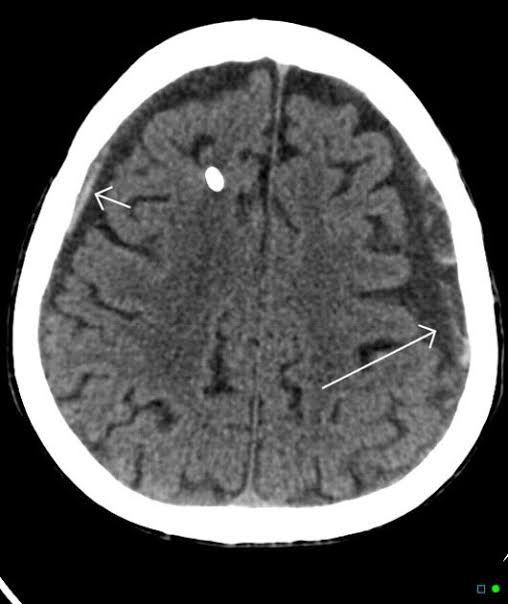

A chronic subdural hematoma (SDH) is a collection of blood on the brain’s surface, under the outer covering of the brain (dura). It usually begins forming several days or weeks after bleeding initially starts. Bleeding is usually due to a head injury. A chronic SDH doesn’t always produce symptoms. When it does, it generally requires surgical treatment.